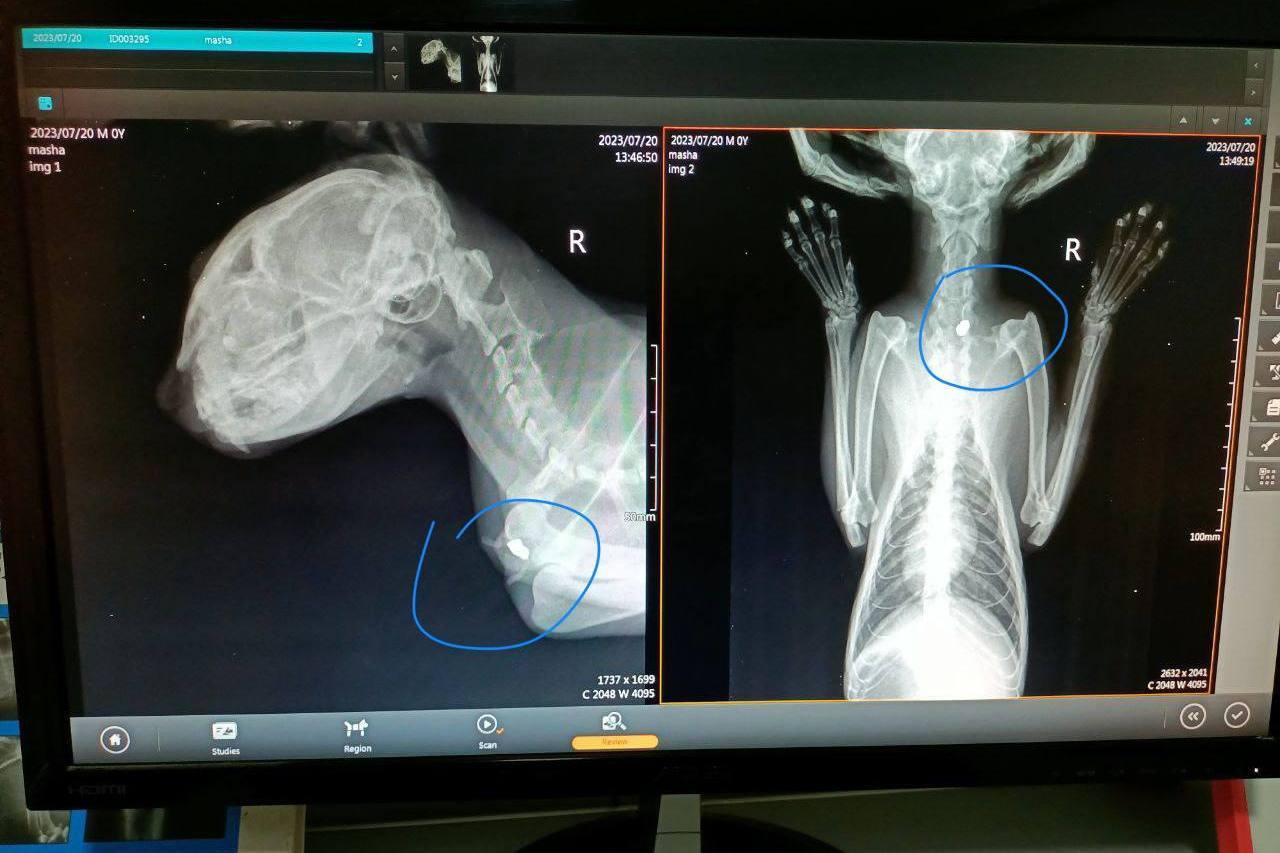

Кошку Машу этим летом нашли в истощенном состоянии в Ортачале. Изо рта у нее текли слюни, она не могла глотать. На рентгене ветеринары обнаружили пулю, которая прошла через щеку, горло и застряла в груди животного.

«В кошку стреляли из пневматического оружия», — рассказал Paper Kartuli волонтер Максим, который курирует лечение Маши в проекте Tbilisi Cat Rescue. Максим приехал в Тбилиси более года назад из России, где 15 лет помогал бездомным животным.

Маша не первая кошка, которая пострадала от людей в этом году. В начале мая волонтеры Tbilisi Cat Rescue обнаружили кота Лешего с заросшей пулей в голове в Ботаническом саду, в июне — избитого кота, который лишился глаза, а в августе — раненого кота с пулей в щеке.

Из-за ранения у кошки Маши развилась сильная бактериальная инфекция, ослаб иммунитет, у зверя обнаружили иммунодефицит и инфекционно-вирусный перитонит, говорит Максим.